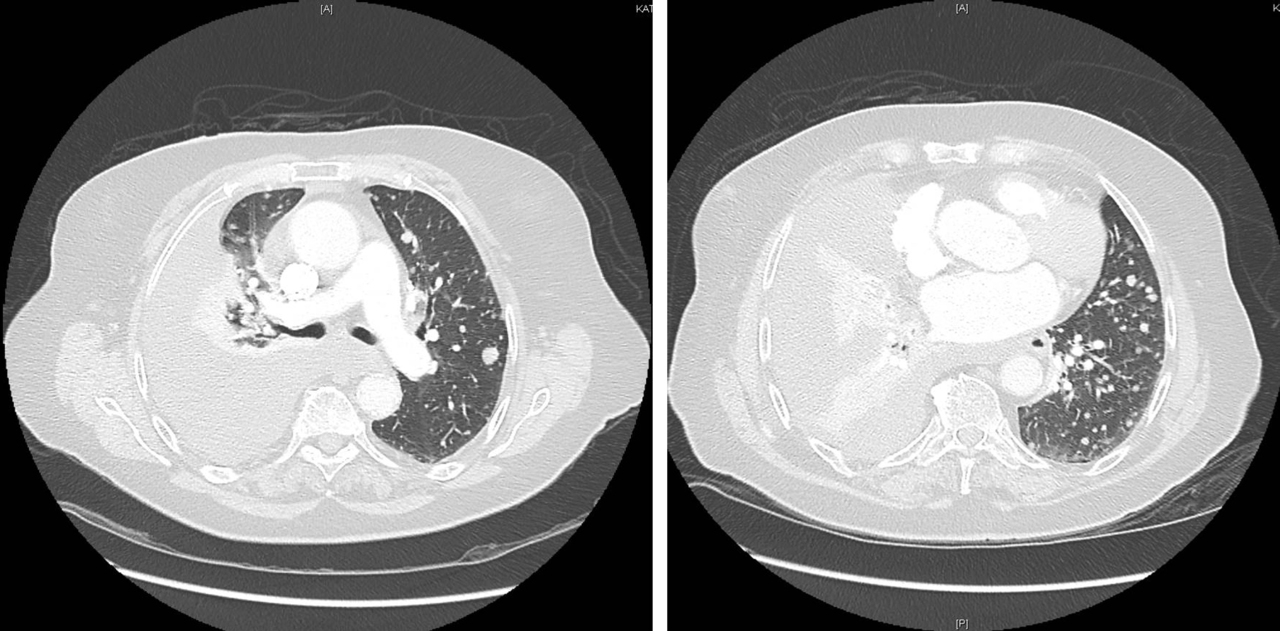

Mme K. est admise aux urgences pour exploration d’une douleur thoracique. Cette femme de 76 ans est suivie en cardiologie depuis dix ans pour un rétrécissement aortique, une hypertension artérielle (HTA) et une dyslipidémie. Elle est parfaitement autonome à domicile. Elle fume un demi-paquet de cigarettes par jour depuis trente ans. Elle est traitée par rivaroxaban (anti-Xa) depuis six semaines pour une thrombose veineuse profonde (TVP) du membre inférieur droit survenue à l’occasion d’un voyage en voiture. Le reste de son traitement comporte de la simvastatine et de l’hydrochlorothiazide.

Depuis trois jours, elle présente une douleur thoracique croissante, latéralisée à droite et survenue sans facteur déclenchant évident.

À évoquer en priorité car TVP récente et douleur thoracique. Le traitement anticoagulant en cours n’élimine pas une migration embolique (surtout en cas de mauvaise observance).

À évoquer devant une douleur thoracique latéralisée.

À évoquer devant une douleur thoracique latéralisée chez une patiente avec tabagisme important.